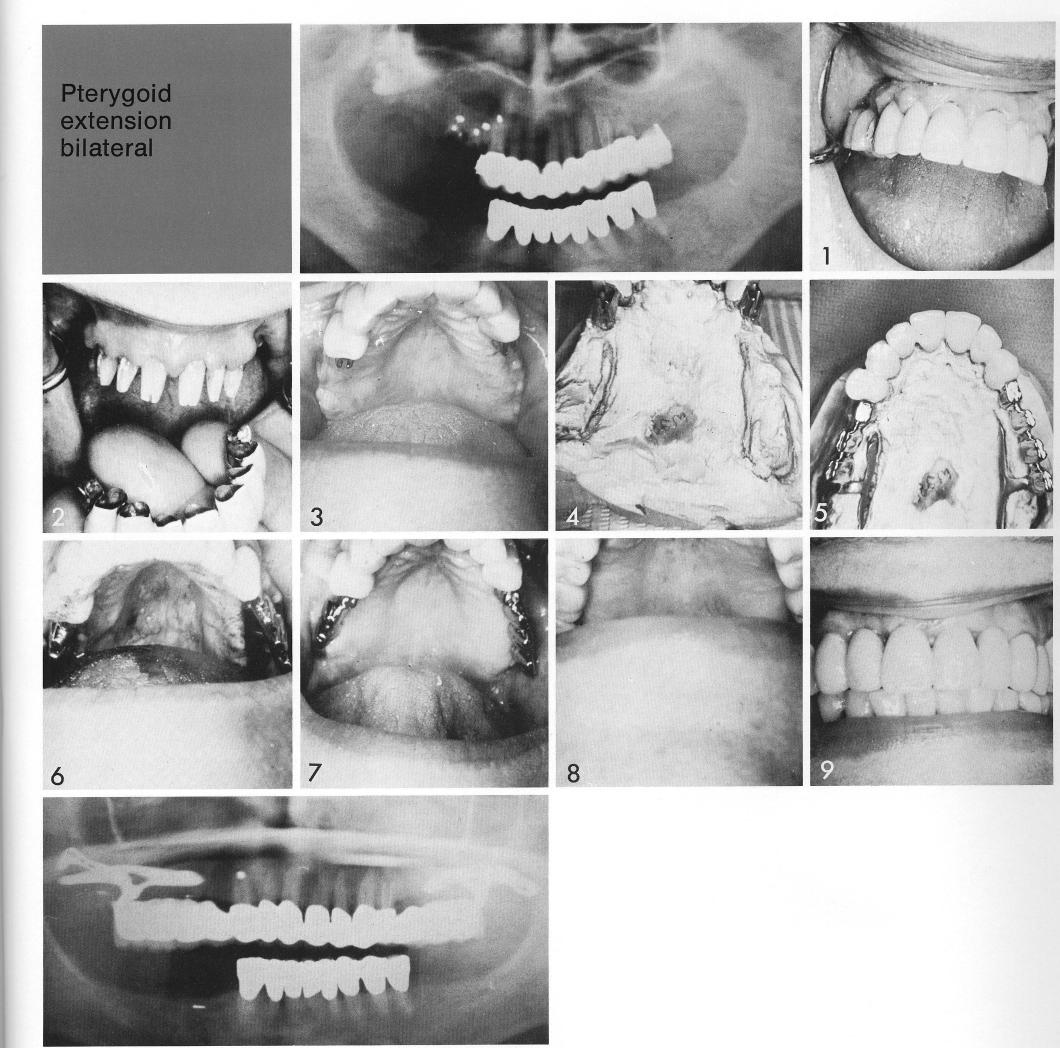

Pterygoid extension bilateral

The teeth were prepared (1,2), and attachments cantilevered from the restoration (3). The bilateral pterygoid extension implants were designed on the stone model (4,5) and inserted (6). Healing was uneventful (7), and the insertion of the final splints completed the case (8,9).

1 Bilateral maxillary pterygoid extension implants design on stone model